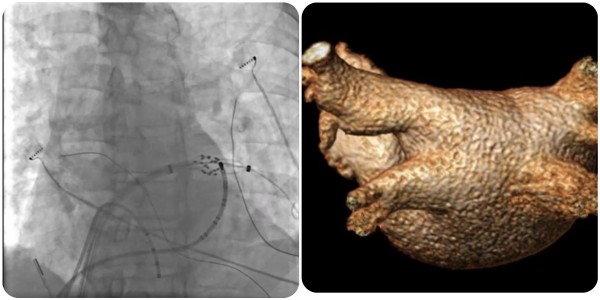

近日,糖心vlog (简称中山一院广西医院)心血管内科团队完成广西首批三维标测系统指导下经皮导管脉冲电场消融术(即CardiPulse脉冲电场消融系统上市后广西首批应用),为一名阵发性房颤患者进行了房颤脉冲电场消融治疗,成功帮助患者恢复正常心律。

在夏文豪的指导下,我院心血管内科心律失常介入团队为患者制定了个性化诊疗方案,并联系介入导管中心、重症医学科、心胸外科、手术麻醉中心做好应急预案,为手术全程保驾护航。手术仅2小时,消融过程中患者心律转为正常,肺静脉即刻隔离,术后恢复良好,目前已康复出院。

脉冲电场消融(Pulsed Field Ablation,PFA)利用短时程、高电压的多个电脉冲释放消融能量,可在细胞膜上产生不可逆的纳米级微孔,导致细胞死亡,可用于房颤导管消融,实现肺静脉隔离。